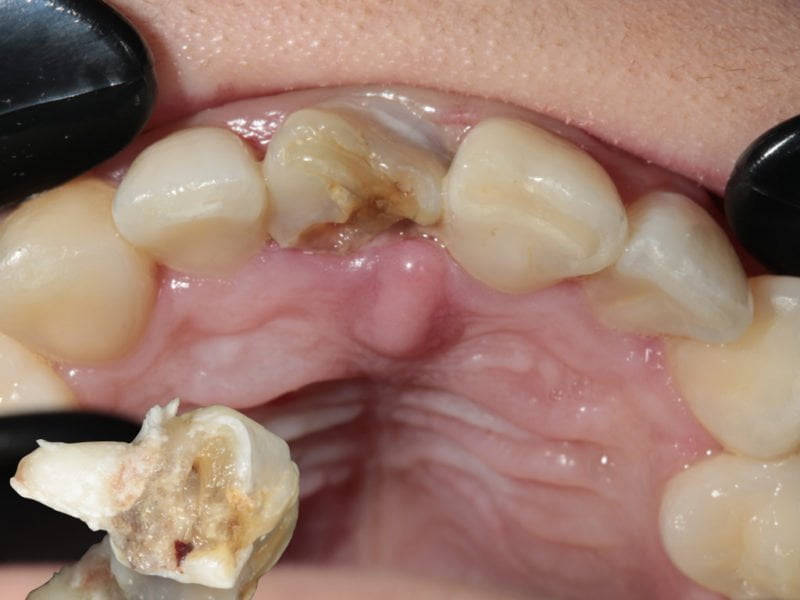

The patient came to our attention with a periodontal problem concerning element 1.1. After a radiographic check-up we confirmed a treatment plan that required the extraction of the tooth, the removal of the below cyst and the direct insertion of a slim implant in the same site. In order to maintain the soft tissues natural appearance we decided to perform some bone grafting. As the implant is in an aesthetically important position we inserted in a provisional tooth in same session.